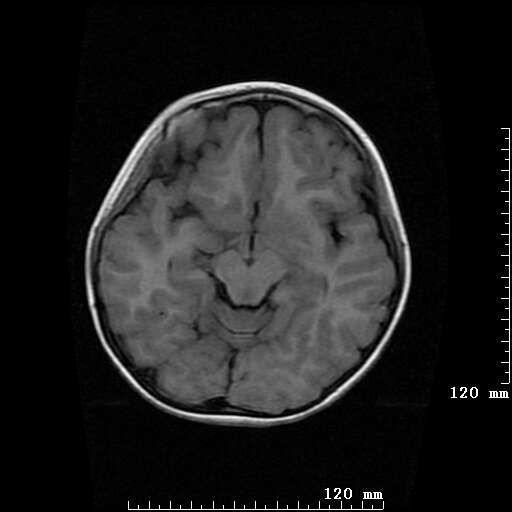

女,7岁,三岁才说话、走路。现智力尚可,走路不稳。临床怀疑大脑发育不全。

考虑 脑白质发育不良

脑折质变薄,双侧侧脑室稍扩张,支持考虑脑折质发育不良

侧脑室周围白质软化症。

考虑胼胝体发育不全,髓鞘形成不良。

支持考虑胼胝体发育不全,髓鞘形成不良。

脑裂畸形伴灰质异位

侧脑室周围白质数量减少,侧脑室不对称性扩大,左侧侧脑室后角呈方形改变,脑沟加深,结合临床考虑脑室周围白质软化症(pvl)。期待结果!

只看出灰质异位

支持脑白质发育不良。